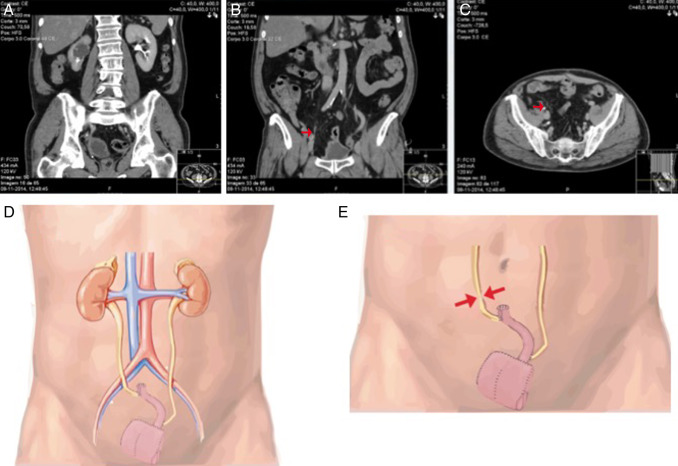

Foram realizados 2 procedimentos de reimplantação ureteral laparoscópica. Os doentes tinham sido previamente submetidos a cistectomia radical laparoscópica, com confeção de neobexiga ortotópica. Ambos os doentes desenvolveram uretero‐hidronefrose direita (fig. 1 ) cerca de um ano após a cistectomia radical, com necessidade de colocação de nefrostomia percutânea temporariamente. Nos 2 casos foi realizada uma tentativa de tratamento endoscópica (dilatação endoscópica anterógrada), mas sem sucesso, tendo sido proposto aos pacientes a realização de uma correção laparoscópica.

Nesta figura observamos em tomografia a presença de uretero‐hidronefrose direita ...

Nesta figura observamos em tomografia a presença de uretero‐hidronefrose direita (A) e a provável localização da estenose (B e C – setas vermelhas). Em D está patente, de forma esquemática, a forma de confeção da neobexiga ortotópica. Em E é visível, de forma esquemática, a provável localização da estenose neste caso clínico particular (setas vermelhas).